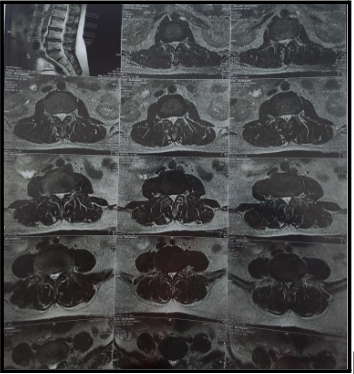

Since an MRI (Magnetic Resonance Imaging) produces incredibly detailed images of the soft tissues, nerves, and spinal discs, it is typically the first option. While piriformis syndrome may not directly cause changes in the spine, it may cause inflammation around the muscle area. On MRI, a herniated disc pressing on the sciatic nerve root will usually be seen.

This MRI reveals:

- No evidence of fracture, listhesis or generalized marrow abnormalities.

- However, diffuse posterior annular bulge of L3-4 intervertebral disc is causing compression of the thecal sac and indentation of lateral recesses.

- Circumferential bulge of L4-5 intervertebral disc causes compression of thecal sac, bilateral lateral recesses and indentation of transiting nerve roots along with moderate narrowing of the spinal canal.

- Right posterior para central bulge of L5-S1 intervertebral disc causes effacement of epidural fat

- Compression of right lateral recess & right transiting S1 nerve roots

- Moderate narrowing of CSF column is seen on MR myelogram

- Anterior & posterior osteophyte formation is seen at L3, L4 & L5